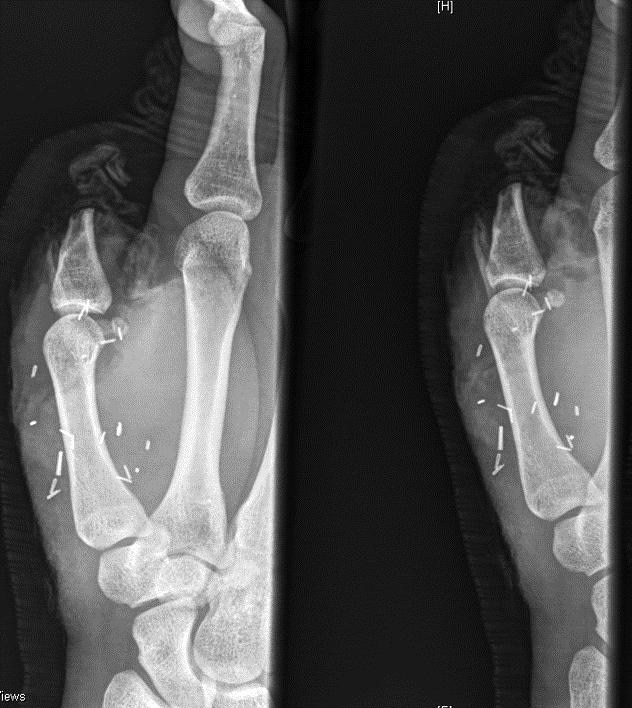

وی قبل از این که تحت عمل پیوند قرار بگیرد، دو عمل جراحی ناموفق برای اتصال مجدد انگشت شست به دستش داشت.

عمل پیوند انگشت شست پا با انگشت شست دست «زک» که در بیمارستان سیدنی استرالیا صورت گرفت 8 ساعت به طول انجامید.

بیمارستان سیدنی مدعی شده است که این عمل پیوند بیسابقه بوده است.